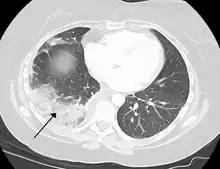

Chest CT (axial lung window)

Chest CT (coronal lung window)- Chest CT (axial lung window)

A lung contusion is a bruise caused by chest trauma. It results in hemorrhage of the alveoli causing a build-up of fluid which can impair breathing, and this can be either mild or severe. The function of the lungs can also be affected by compression from fluid in the pleural cavity pleural effusion, or other substances such as air (pneumothorax), blood (hemothorax), or rarer causes. These may be investigated using a chest X-ray or CT scan, and may require the insertion of a surgical drain until the underlying cause is identified and treated.[74]

Lung cancer can either arise directly from lung tissue or as a result of metastasis from another part of the body. There are two main types of primary tumour described as either small-cell or non-small-cell lung carcinomas. The major risk factor for cancer is smoking. Once a cancer is identified it is staged using scans such as a CT scan and a sample of tissue from a biopsy is taken. Cancers may be treated surgically by removing the tumour, the use of radiotherapy, chemotherapy or a combination, or with the aim of symptom control.[74] Lung cancer screening is being recommended in the United States for high-risk populations.[94]